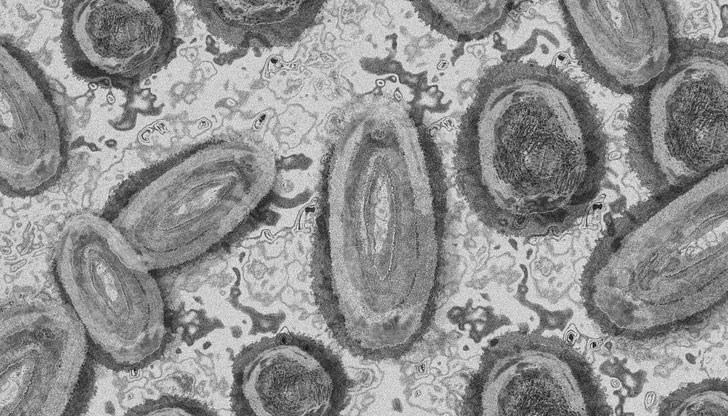

Испания регистрира втори смъртен случай от маймунска треска

Смята се, че двата смъртни случая от заразата в Испания са първите потвърдени от началото на разпространението на болестта в Европейския съюз. Министерството не даде повече подробности за починалия. Вчера то съобщи за първия регистриран смъртен случай от маймунска треска в страната.

През вчерашния ден испанското здравно министерство съобщи, че общо 4298 души в страната са заразени с вируса, което поставя Испания на челно място сред европейските страни по брой регистрирани случаи на заразата. От всички отчетени случаи близо 3500 са на мъже, които са имали полови контакти с други мъже, а само 64 случая са на жени.